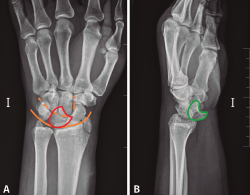

Se solicitó una radiografía anteroposterior y lateral pura de muñeca izquierda, en la que se observa una luxación transestiloperilunar (Figura 2).

Figura 2. A: radiografía anteroposterior en la que se observa la disrupción de los arcos de Gilula. Semilunar en flexión volar (rojo); B: radiografía lateral pura de muñeca en la que se observa la pérdida de la congruencia semilunar, hueso grande y 3.er metatarsiano (verde).

Confirmaremos el diagnóstico con una radiografía anteroposterior y lateral pura de muñeca, observándose una disrupción del arco mayor y menor del carpo, con la luxación del hueso grande de la superficie articular del semilunar y pérdida de altura del carpo. Es importante una correcta realización de las proyecciones para una buena interpretación de las mismas.

Figura 4. A: radiografía anteroposterior de luxación transestiloperilunar; B: radiografía anteroposterior sin alteraciones, recuerdo anatómico. 1: estiloides radial; 2: estiloides cubital; 3: escafoides; 4: semilunar; 5: piramidal; 6: pisiforme; 7: ganchoso; 8: grande; 9: trapecio; 10: trapezoide; 11: primer metacarpiano; 12-15: segundo a quinto metacarpianos; —: almohadilla grasa; —: eje longitudinal 3.er radio, muñeca y antebrazo; —: arcos de Gilula.

- Qué ver en una radiografía anteroposterior de muñeca (Figuras 4A y 4B). Para valorar que estamos ante una correcta proyección, debemos obtener:

– Una vista anteroposterior de la región media de los metacarpianos, del carpo, de la articulación radiocubital distal.

– La forma de la diáfisis de los metacarpianos debe ser cóncava.

– Debe existir una separación del radio y cúbito distales (puede existir una superposición mínima).

– Por último y más importante, el eje longitudinal del 3.er radio, la muñeca y el antebrazo deben quedar alineados.

En la radiografía podemos observar los siguientes ítems:

– Observar la alineación correcta de las articulaciones.

– Buscar interrupciones en las corticales de los huesos que nos puedan hacer sospechar una fractura.

– Afectación intraarticular.

– Pero, en especial, debemos fijarnos en los arcos de Gilula, deben formar 3 líneas continuas, sin disrupciones. En las luxaciones se pierde la continuidad de las líneas que forman los diferentes arcos.

- 1.er arco: superficie proximal del escafoides, semilunar y piramidal.

- 2.º arco: superficie distal del escafoides, semilunar y piramidal.

- 3.er arco: superficie proximal de grande y ganchoso.